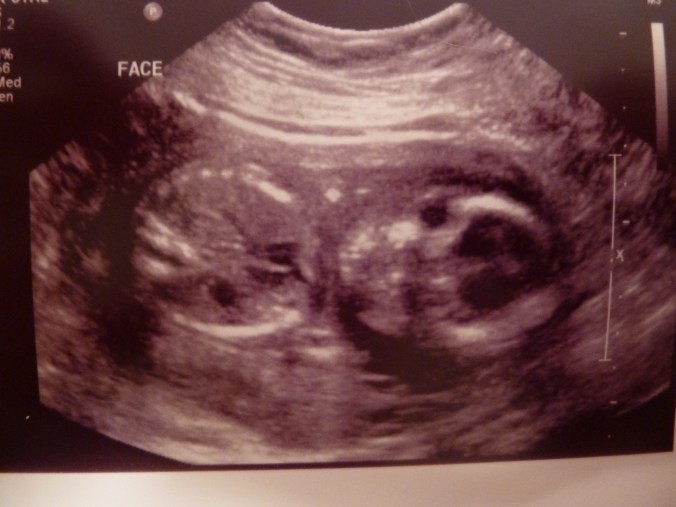

So, I had my big 20-week sonogram this afternoon and…

P1160894

The best news of all is that baby #3 looks perfectly healthy. (And judging from all the jumps I’m feeling, also quite happy!)

P1160893

Just like my first two, this one didn’t cooperate too well with the test. It took three goes for the technician to get all the information she needed.

P1160892

However… baby wasn’t at all shy about revealing gender.